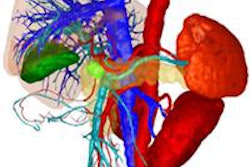

The institute said that Kikinis intends to create new synergies by bringing American and European researchers closer together. On the technology side, Kikinis will work on enhancing interoperation between the 3D Slicer software package and the MeVisLab software.